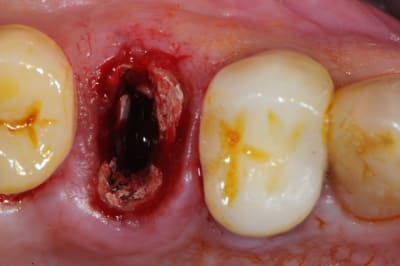

ton intervention, albert, me rappel un cas clinique que j'aimerai partager avec vous:

1-2-3 prémolaire foutu juste à proximité d'un implant, faut donc faire gaffe aux tissus environnant.

en plus je suis sure que la corticale vestibulaire est K.O elle aussi.

4-5: eh ben oui, elle est détruite! une simple curette insérée dans l'alvéole permet de visualiser l'importance de la perte osseuse vestibulaire.

que faire ??

C'est une excellente indication: la racine est très ovalaire, la corticale est absente, la position de l'implant sera très en dedans du boitier osseux.

Si tu poses l'implant immédiatement tu auras sans doute un bon résultat mais tu perdras la convexité vestibulaire et tu auras une fibrose au contact de la partie vestibulo-coronaire de l'implant.

Dans quelques années on parlera de periimplantite alors qu'il s'agit d'une erreur technique...que l'on peut éviter avec une membrane qui supporte l'exposition.